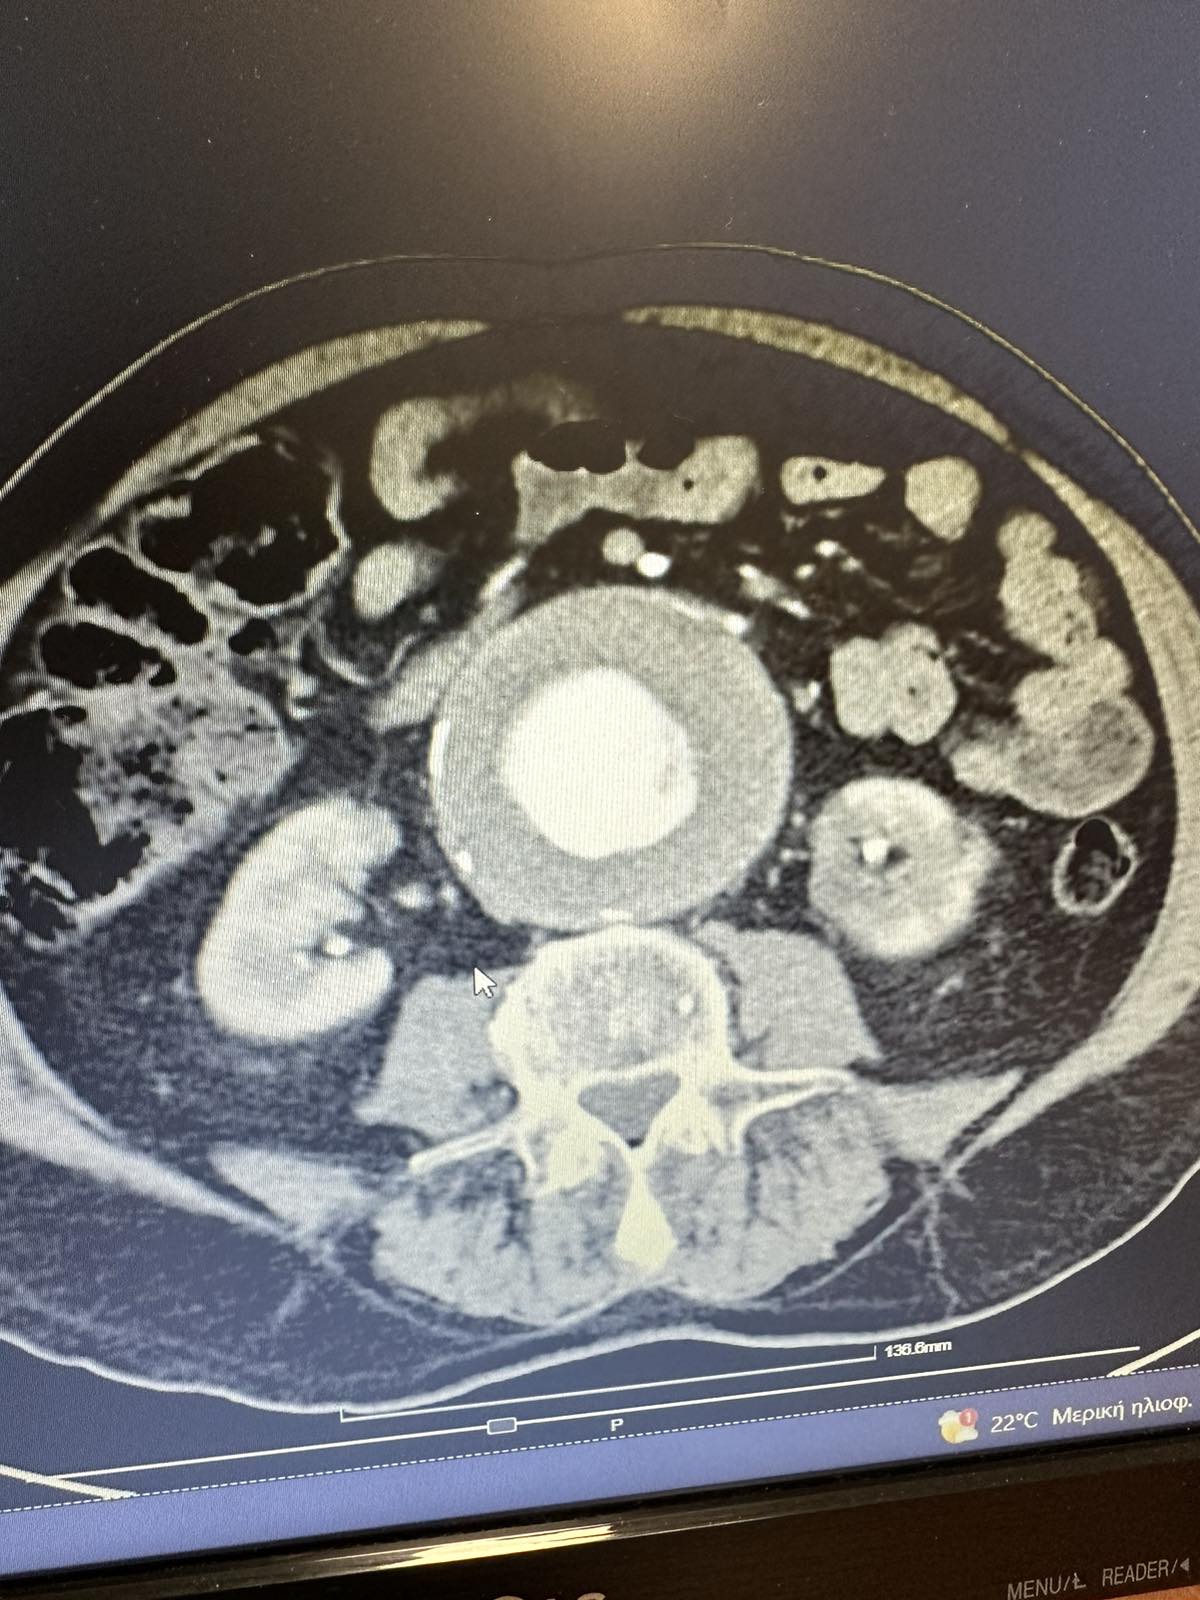

Η διάγνωση του ανευρύσματος κοιλιακής αορτής γίνεται με triplex κοιλιακής αορτής ή αξονική τομογραφία κοιλίας. Κάθε άνθρωπος (στο πλείστο των περιπτώσεων άνδρας) που υπερβαίνει το 60ο έτος της ηλικίας του πρέπει να ελέγχεται με triplex κοιλιακής αορτής (εάν έχει 1ου βαθμού συγγενή με ανεύρυσμα κοιλιακής αορτής η εξέταση πρέπει να γίνει μετά το 50ο έτος). Σε ασθενείς που χρειάζονται αποκατάσταση του ανευρύσματος κοιλιακής αορτής η πιο λεπτομερή προεγχειρητική εξέταση είναι η αξονική αγγειογραφία κοιλιακής αορτής και λαγονίων. Σε ασθενείς που δεν μπορούν να υποβληθούν σε αξονική αγγειογραφία διενεργείται μαγνητική αγγειογραφία κοιλιακής αορτής και λαγονίων.

Ο κίνδυνος ρήξης του ανευρύσματος κοιλιακής αορτής είναι ανάλογος με τη διάμετρο του. Για ανευρύσματα κοιλιακής αορτής μικρότερα των 5εκ. το μόνο που απαιτείται συνήθως είναι περιοδικός έλεγχος με triplex (ή αξονική τομογραφία), έλεγχος αρτηριακής υπέρτασης και διακοπή του καπνίσματος.

Θεραπεία χρειάζεται όταν η διάμετρος γίνει μεγαλύτερη των 5εκ. , όταν υπάρξει μεγάλη αύξηση σε δύο διαδοχικές μετρήσεις ή όταν το ανεύρυσμα προκαλέσει συμπτώματα.